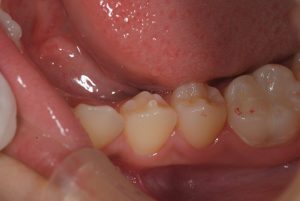

次に、別の患者さんの例です。

左下の痛みに襲われ歯医者さんに行くものの、特に原因が認められないため様子を見ましょうと言われていたということで、3件目で当医院に来ていただきました。

歯を見てみると中心結節が折れており、X線写真をとってみると神経が死んでしまい、左下の小臼歯から膿がたまっていた状態でした。

まさに、中心結節が原因となっていた状態でした。